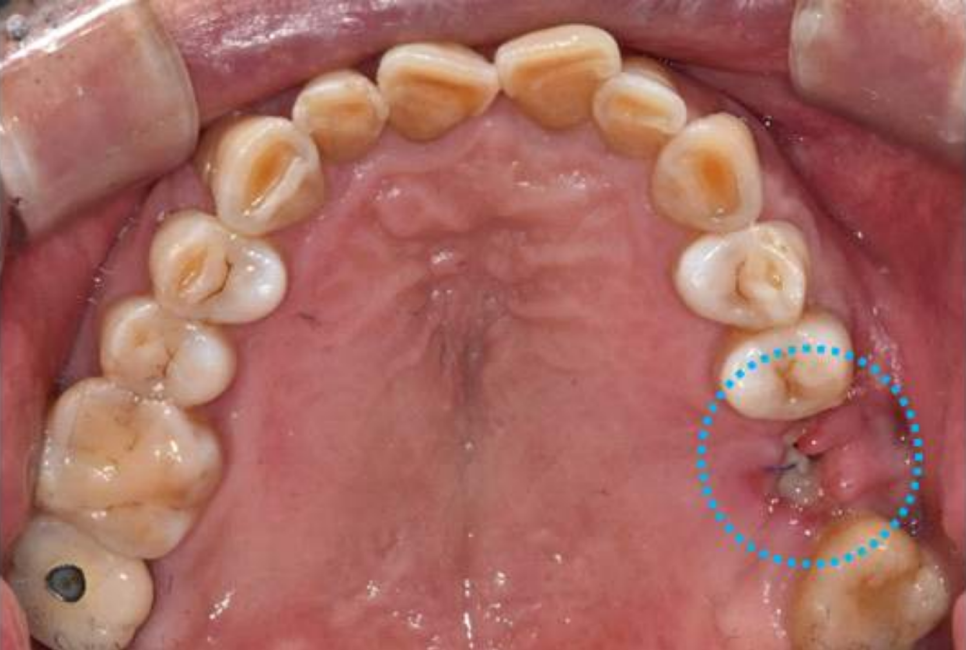

왼쪽 위 잇몸이 부었다고 내원하셨는데요

엑스레이와 입안을 같이 보니

왼쪽 어금니는 이미 발치한 상태였고

봉합해 놓은 실이 남아 있었습니다.

하지만 아직 치유가 완전치 않은 상태였고고

통증으로 불편해하시고 계셨습니다.

파노라마 엑스레이 상에서 좋지 않게 보이는

오른쪽 아래 어금니도 같이 설명드렸습니다.

오른쪽 아래 어금니 같은 경우는

그냥 눈으로 봤을 때는 크라운 보철이 되어 있기 때문에

상태가 너무 좋아 보이지만

엑스레이상으로 보면 뿌리에 길게 신경치료 한 부분이 보이고

"뿌리 끝 염증으로 주변 뼈가 까맣게 녹고 있는 모습"이 보입니다.